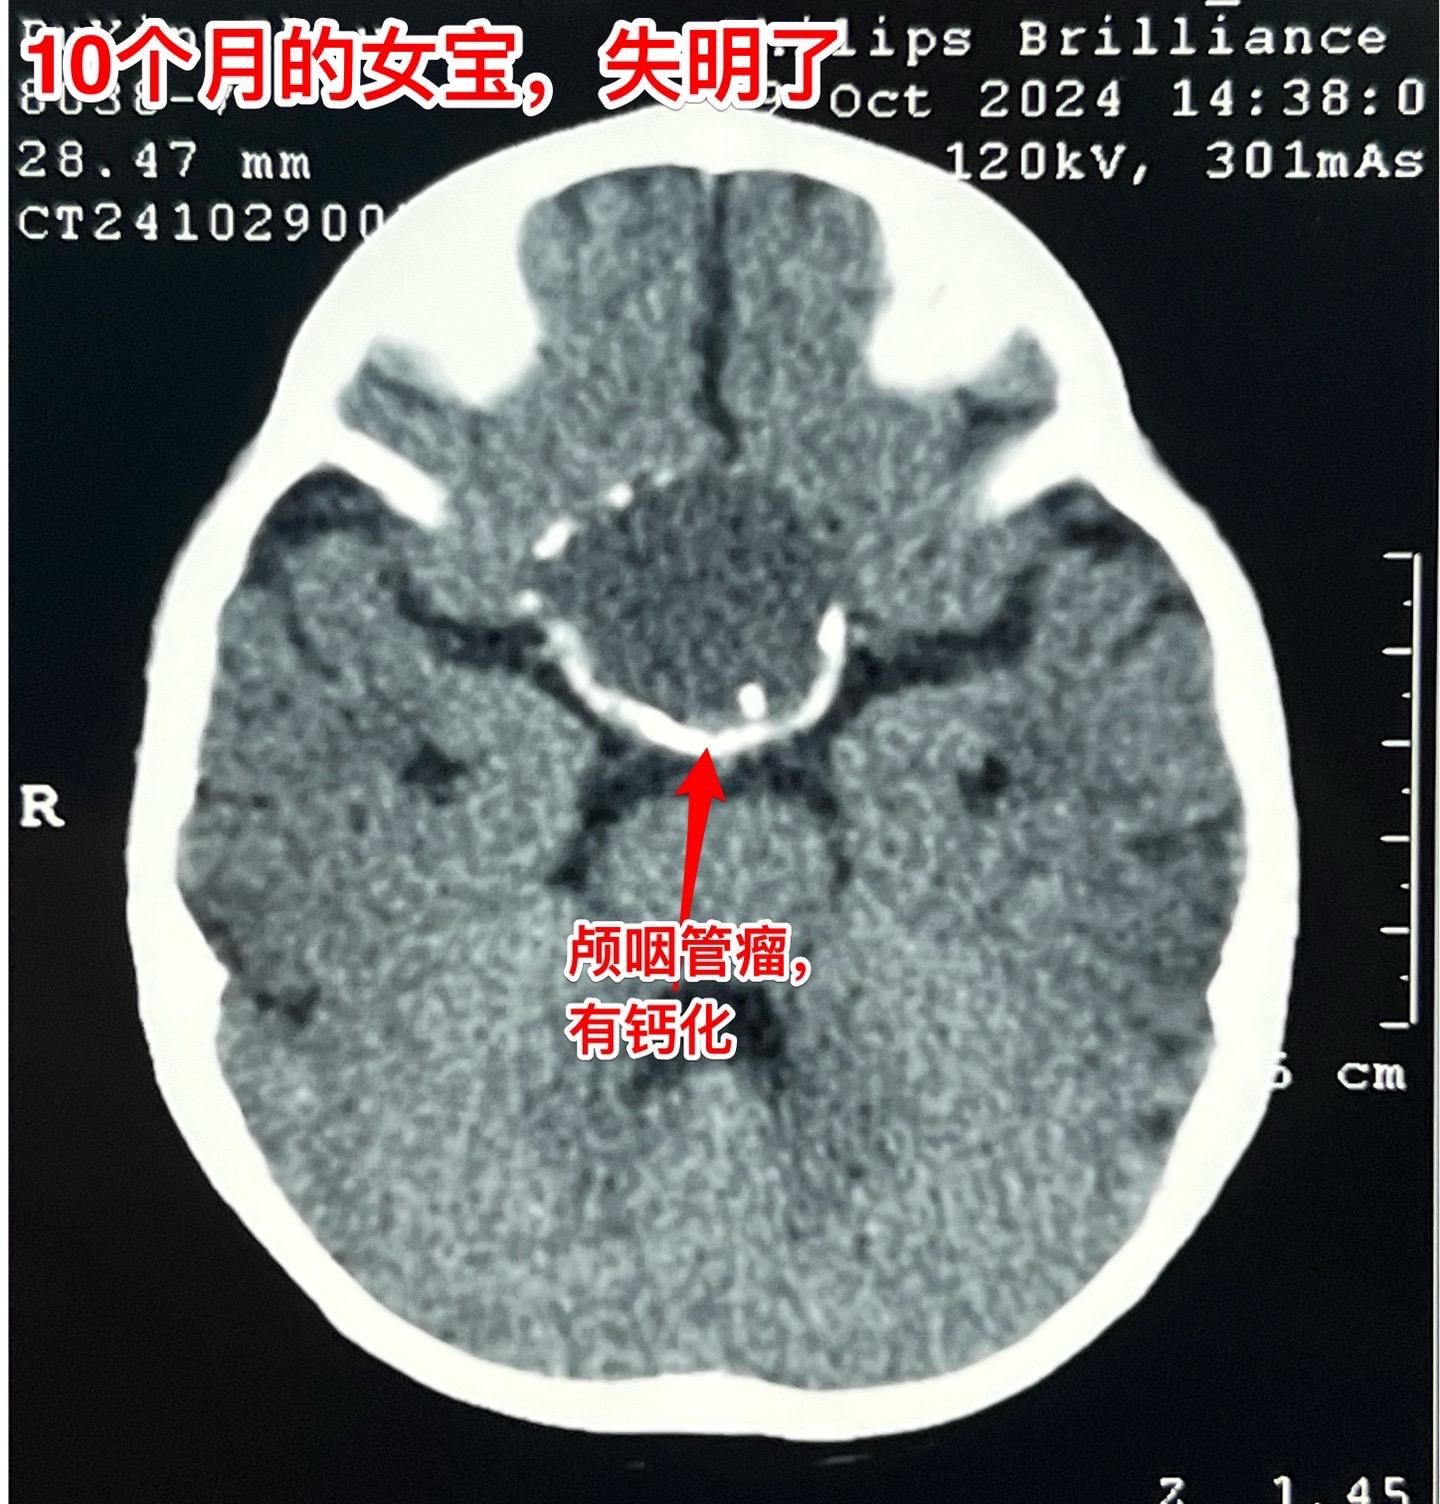

10个月大的宝宝视力下降能不能被家长发现。可以肯定,10个月大的宝宝,无论他有多高的语言天赋,也不会表达视力下降! 所以,对于还不能说话的小宝宝,家长对眼睛的观察就要时时细心才行。 细心的观察一定能发现视力下降的蛛丝马迹! 在两个月前,家长就发现这个成都的女宝眼睛似乎不能追随物体或人物而转动!到眼科去检查,作了磁共振就发现了脑部肿瘤,见图。再结合CT就可以确诊颅咽管瘤了。10.28来住院,住院的时候小朋友的双侧瞳孔对光反应消失了,也就是说已经双目失明了!